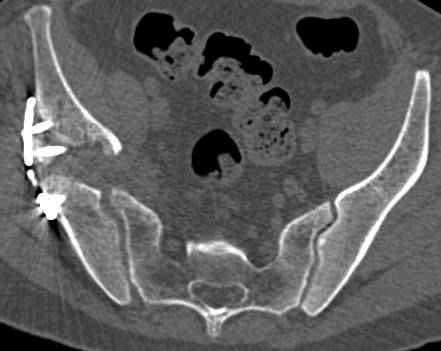

высылаю дополнительно сканы.

итак, второй вариант: высокий двухколонный с вовлечением КПС... Ни одно из основных повреждений не репонировано, кроме задней стенки. Скорее всего попытка реконструкции вертлуги сейчас будет очень травматичной и не очень эфективной, т.е. вероятный риск более значим, чем ожидаемая польза... Лучше подождать, и потом сразу эндопротез